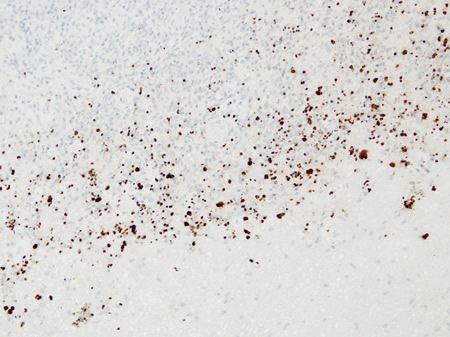

Biópsia de paciente com vírus da imunodeficiência humana (HIV) com toxoplasmose, com os taquizoítos identificados usando imuno-histoquímica

Do acervo pessoal de Robert E. Schmidt; usado com permissão